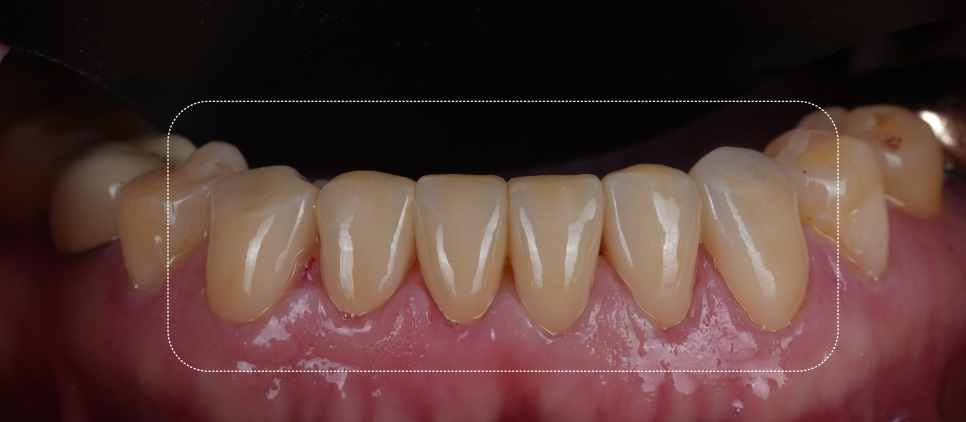

아래 앞니는 치아 윗부분(절단면)이 많이 닳아서 길이가 눈에 띄게 짧아져 있었고, 닳아 없어지면서 사이사이에 빈 공간이 보였어요.

뿐만 아니라, 치아 겉 부분(법랑질)이 모두 닳아 신경과 가까운 상아질이 모두 노출되어 있었는데요.

이렇게 상아질이 노출되어 있으면 시린 증상이 나타나며, 장기간 지속될 경우 신경까지 괴사될 수 있어 치료가 시급한 상황이었습니다.

촬영일 : 251013

또, 아랫니가 많이 닳아있어 깊게 무는 형태인 'Deep bite(딥바이트)' 라고 부르는 과개교합 상태였죠.

오랜 시간 서로 부딪히며 위아래가 서로를 갈아버린 흔적이죠.